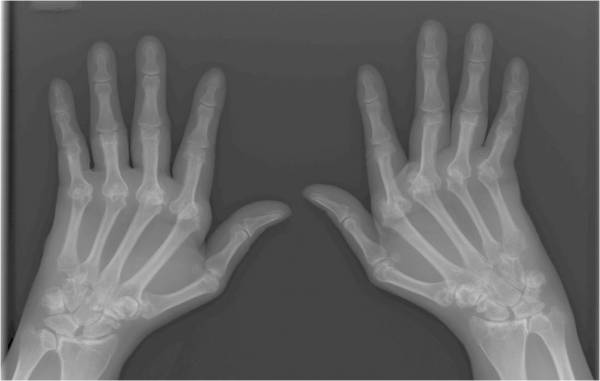

Reumatoidni artritis prvenstveno zahvaća male zglobove u rukama i nogama. Također reumatoidni artritis djeluje na oštećene zglobove ili one koje najčešće koristimo kao što su zglobovi na stopalima, koljenima i ramenima. Reumatoidni artritis koji je zahvatio ruke uglavnom zahvaća dominantnu, desnu ruku.

neki fizikalni, laboratorijski i radiografski testovi potvrđuju dijagnozu u odbacuju druge bolesti. Ti testovi uključuju :

-snimke poput rtg snimki ili elektroničnog spina